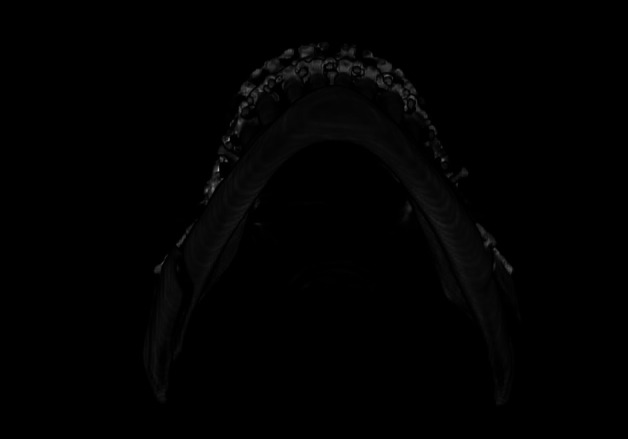

Material and methods: A retrospective analysis was conducted on 157 patients (314 osteotomies) over five years. Multi-slice helical CT scans, both pre- and post-operative, were examined to classify BS and identify potential risk factors. Anatomical variables included the presence of third molars, edentulism, prior fixation systems, mandibular ramus dimensions, lingula position, and alveolar crest height. Technical aspects of osteotomy execution were also assessed. Measurements were performed using Dolphin Imaging Software 11.95 after orienting the skull in the Natural Head Position.

Results: The incidence of BS was 3.2% (10 patients), with a slight left-side predominance (60%). Class A BS (distal fracture of the proximal segment) was the most common (60%). Anatomically, 83.3% of Class A cases had a more anteriorly positioned lingula and 66% presented a lower alveolar crest. Technically, 80% of BS cases showed deviations in osteotomy execution, with incomplete osteotomy at the basal level being the most frequent (60%).